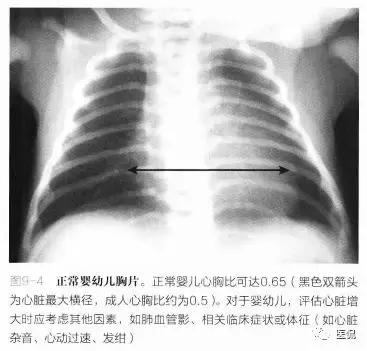

■与成人相比,正常新牛儿和婴儿心脏相对胸廓较大。正常婴幼儿心胸比可达0.65(图9-4),而成人心胸比大于0.5属于异常。这是由于新生儿不能像成人一样深吸气,他们的腹部与胸部的相对比例与成人不同。

■在评估婴幼儿心影增大时,应考虑其他因素,如肺血管影、相关临床症状或体征(如心脏杂音、心动过速、发组)。

诊断误区:儿童的胸腺可能部分与心脏重叠,I有时会误认为是心影增大。通常,3岁前可在胸片上看到胸腺,也有到8岁时仍可见的。正常胸腺稍呈分叶状,尤其是在肋凹处(图9-5)。